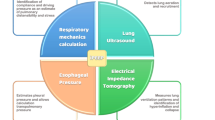

Currently, we can perioperatively employ devices such as electrical impedance tomography (EIT) that analyses lung regional ventilation [9], oesophageal pressure (Pes) monitoring which reflects approximately the pleural pressure, allowing transpulmonary pressure (Ptp) estimation [10], and lung and diaphragmatic ultrasound (US) that enable us to assess the echogenicity of the different lung fields to quantify aeration [11] or to assess diaphragmatic functionality [12]. This raises the question of whether and when these advanced respiratory monitoring tools should be used to prevent PPCs.

Advanced Respiratory Monitoring Tools Pros and Cons

Electrical Impedance Tomography

EIT is a non-invasive technique for monitoring lung ventilation as well as ventilation-perfusion mismatches. Electrodes are placed on the chest and record the surface voltage after repeated application of a small amount of electrical current. It provides images based on the chest tissues’ electrical conductivity [33]. The changes in electrical impedance are displayed as colour-coded images, providing a pixelated mapping of regional lung ventilation, thus adding information about the homogeneity of lung ventilation on a breath by breath [34]. EIT assesses hypoventilation, overdistension and areas of heterogeneous ventilation, allowing the clinician to estimate lung recruitability [35]. This technique has been used intraoperatively to individualize ventilator settings such as PEEP and VT [36,37,38,39], and in the postoperatively to assess the distribution of ventilation and to identify atelectatic regions [40, 41]. A recent meta-analysis of randomized-controlled trials (RCTs) [42] compared the effect of using EIT or Pes to guide individualized PEEP compared to standard monitoring, so it showed an improvement in intraoperative oxygenation. However, EIT is mostly used for research purposes and there are certain limitations to its routine roll both perioperatively and in critically ill patients [9, 37, 43]. For instance, its resolution is lower than that of other imaging techniques, such as computed tomography [37]. Moreover, incorrect placement of the electrodes can modify the image, affecting its intrapatient reproducibility [44]. Also, it should not be used in patients with pacemakers or automatic defibrillators due to possible interference with such devices [37].

Oesophageal Manometry

During mechanical ventilation, the peak pressure (Ppeak) is the force applied to overcome the airways resistance and inflate the lungs [45]. By setting a brief pause during inspiration, ventilators measure the plateau pressure (Pplat), which helps differentiate the lung’s elasticity from the airway resistance. Thus, Pplat indicates the elasticity of the lung, and the difference with Ppeak is due to airway resistance. The driving pressure (ΔP) that pushes each breath’s VT is the difference between Pplat and the set positive end-expiratory pressure (PEEP) or the intrinsic PEEP if it does exist [45]. The ratio of VT to ΔP indicates the lung’s compliance (C), or its ability to expand, which is the opposite of elastance [45]. Furthermore, lung strain is defined as the lung tissue stretch during each breath and is calculated by comparing the VT per ideal body weight to the end-expiratory lung volume (EELV), largely determined by PEEP [46].

Lung Ultrasound

Lung ultrasound (LUS) is a non-invasive, radiation-free method used to evaluate lung mechanics that enables bedside assessment of pulmonary recruitment [61, 62]. It is based on the varying balances of gas and fluid within the lung parenchyma. Accordingly, three patterns are identified: Pattern A indicates predominant aeration, Pattern B suggests the presence of fluid, and Pattern C occurs when the lung parenchyma is dense, indicating consolidation or collapse [62, 63]. In healthy lungs subjected to mechanical ventilation, this technique aims to differentiate between the amount of aeration and alveolar collapse after analysing all the lung fields, thus assessing recruitability [64] and guiding pulmonary recruitment [61]. LUS not only analyses the lung parenchyma but also assesses with high diagnostic accuracy the presence of other pleural contents, i.e., pleural effusion, or the absence of inter-pleural motion, i.e., pneumothorax, apnoea, selective intubation [63, 65]. The practice of LUS for the diagnosis of pneumothorax has become the method of choice among physicians who can perform bedside LUS [66].

Diaphragm Ultrasound

Ultrasound evaluation of the diaphragm is a non-invasive tool that allows us to assess the functionality of this muscle at the bedside [77, 78]. Within the perioperative setting of major surgeries a decreased inspiratory diaphragmatic dome excursion has been validated as an index of diaphragmatic dysfunction, as it is related to increased PPCs. In critically ill patients, diaphragmatic ultrasound (DUS) plays an established role in the assessment of diaphragmatic function and movement in weaning from mechanical ventilation and to guide rehabilitation in critically ill patients.

Advanced respiratory monitoring tools offer both advantages and limitations: EIT effectively individualizes PEEP titration and assesses regional ventilation, although its lower resolution and dependency on correct electrode placement limit its routine clinical use. Pes helps tailor lung protective ventilation by measuring transpulmonary pressure (Ptp), which is crucial in conditions with increased chest wall elastance, despite its technical complexity and limitations in regional stress assessment. LUS aids in identifying lung atelectasis and guiding mechanical ventilation adjustments, although operator dependency remains a drawback. DUS is useful for assessing diaphragmatic function and detecting diaphragmatic paralysis, which is associated with PPCs.